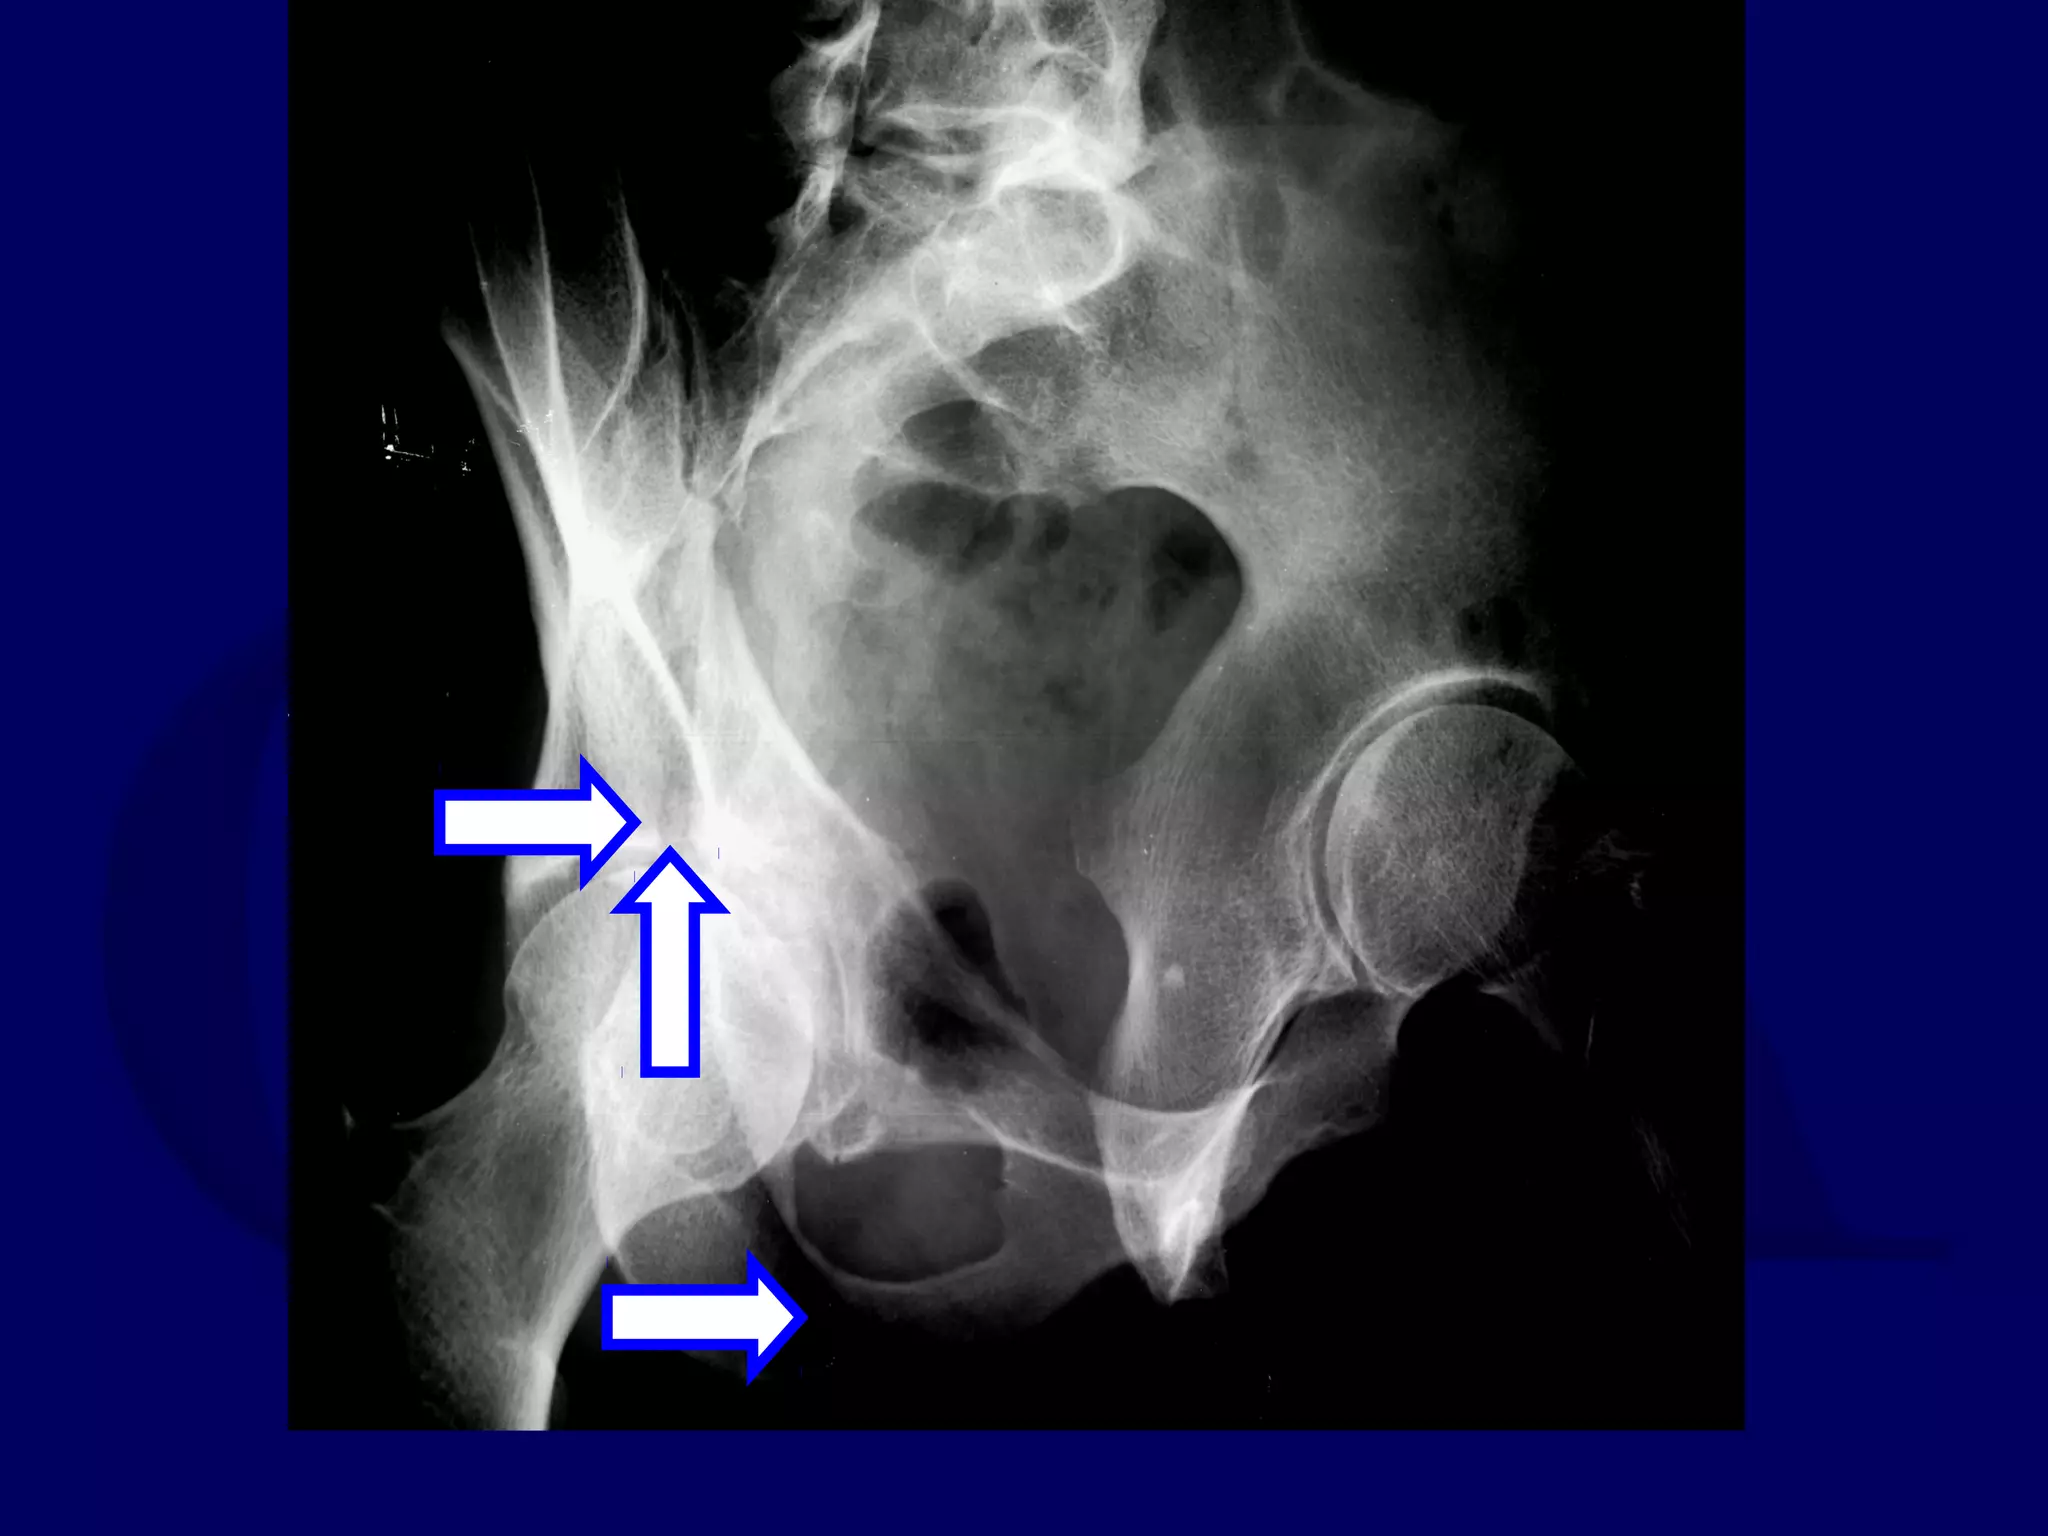

Both Column

Acetabular Fracture

18 Y.O. Female

Isolated Injury

R.C. 00.03.09

SPUR

SIGN